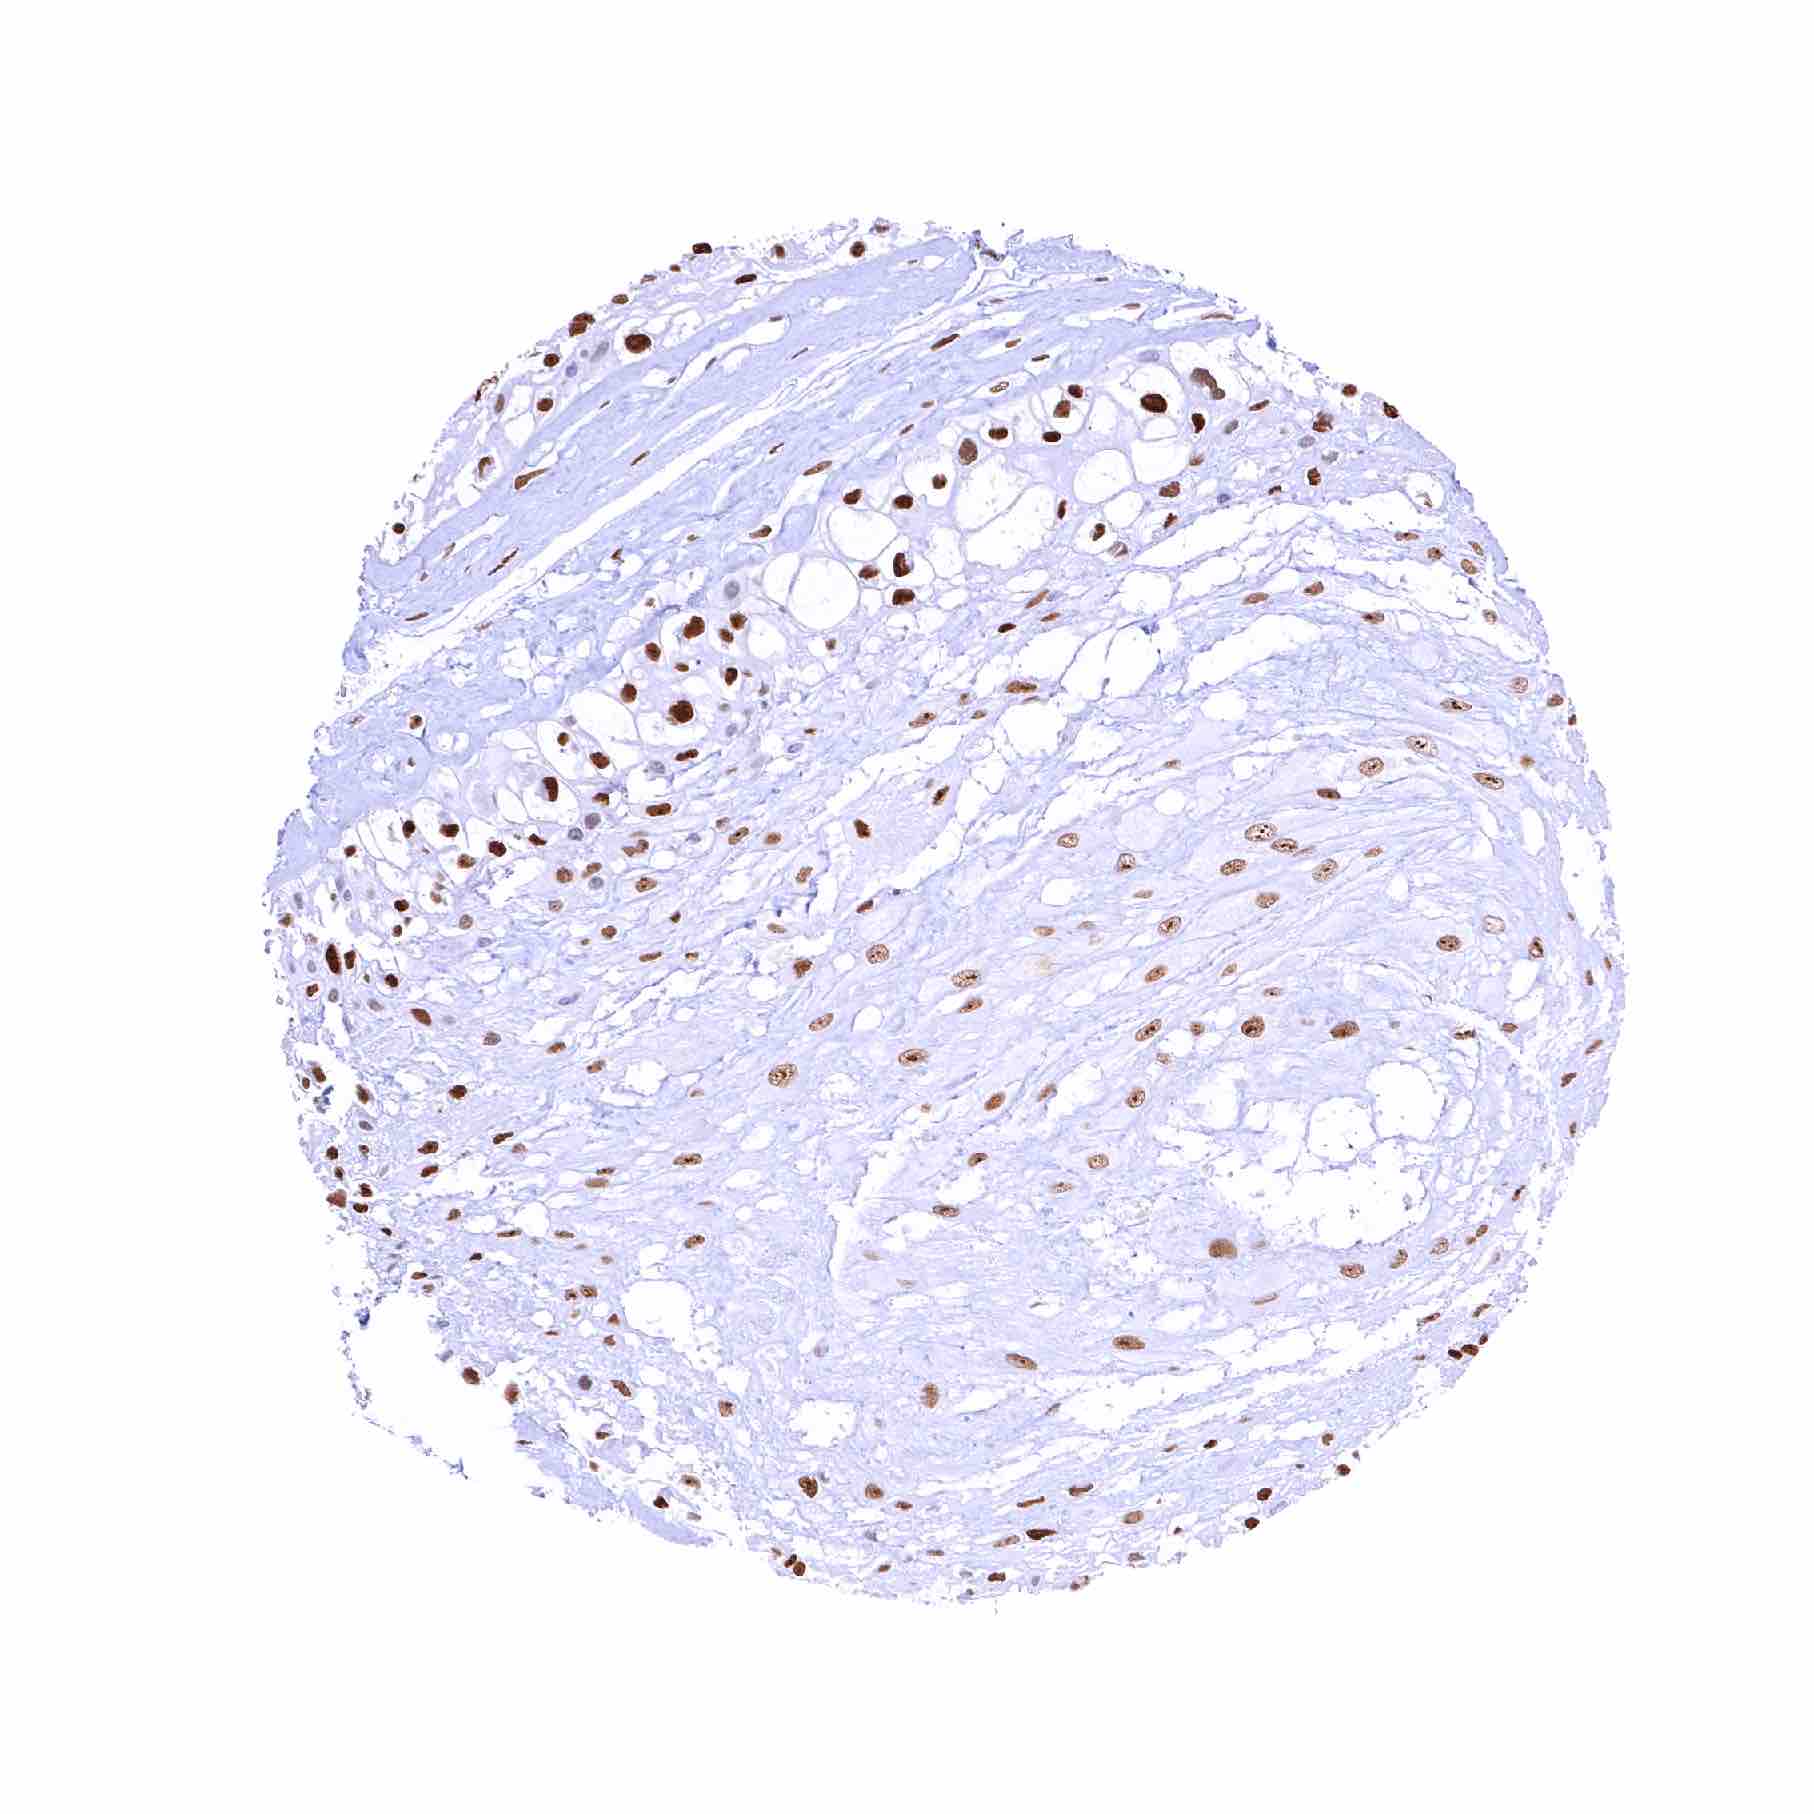

Ovary, stroma